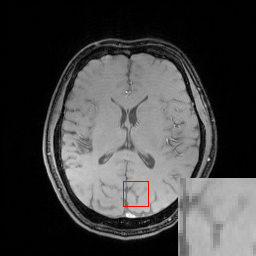

In the CS-MRI inversions, the zero-filled MR images usually serve as the starting point in the iterative optimization. Although the iterative de-aliasing can effectively remove the artifacts and achieve much more pleasing visual quality compared with zero-filled reconstruction, the distortion and information loss is inevitable in the reconstruction. To further illustrate this phenomenon, we compare the pixel-wise reconstruction errors among the zero-filling reconstruction and other reconstruction models of the MR image in Figure 2.

We take the difference between the absolute reconstruction error of zero-filled and the compared CS-MRI methods and only keep the nonnegative values, which can be formulated as

md=(|xfsx¯p||xfs𝒵(y)|)+.subscript𝑚𝑑subscriptsubscript𝑥𝑓𝑠subscript¯𝑥𝑝subscript𝑥𝑓𝑠𝒵𝑦m_{d}={\left({\left|{{x_{fs}}-{\overline{x}_{p}}}\right|-\left|{{x_{fs}}-{\cal Z}(y)}\right|}\right)_{+}}. (8)

Where the operator ()+subscript{\left(\cdot\right)_{+}} set the negative values to zero. We only keep the nonnegative values in the map, which results the filtered difference map. We show the corresponding filtered difference map mdsubscript𝑚𝑑m_{d} in figure 3 in the range [0 0.2]. The bright region means the better accuracy of zero-filled reconstruction. We observe the zero-filling reconstruction provide better reconstruction accuracy on some regions, indicating the information loss in the reconstruction occurs.

Figure 3: The filtered difference map d𝑑d between the reconstruction errors of the zero-filled reconstruction and recent CS-MRI inversions.

To alleviate the information loss in the guide module, we introduce the concatenation operation to utilize the information from both the zero-filled MR image and guidance image as the input to the error correction network. In later Experiment Section V, we further validate it by the ablation study.

To validate the architecture of the proposed DECN model, we conduct the ablation study by comparing the DECN framework with other Baseline network architectures in Figure 4, which we refer the model in Figure 4(a) as DECN with no input concatenation and error correction (DECN-NIC-NEC). With the guide module, a later cascaded CNN module learns the mapping from the pre-reconstructed MR image to the full-sampled MR image. Likewise, we name the models in Figure 4(b) (DECN-IC-NEC) and Figure 4(c) (DECN-NIC-EC). By comparing the DECN-NIC-NEC framework with the DECN-IC-NEC framework, we evaluate the benefit brought by the concatenating the zero-filled MR images and corresponding guide MR images as the input to compensate the information loss in the guide module. In Figure 3, we give the illustration the information from zero-filled MR images and guide images can be shared. By comparing the DECN-NIC-NEC framework with the DECN-NIC-EC framework, we evaluate how the error correction strategy improves the reconstruction accuracy compared with simple cascade manner.